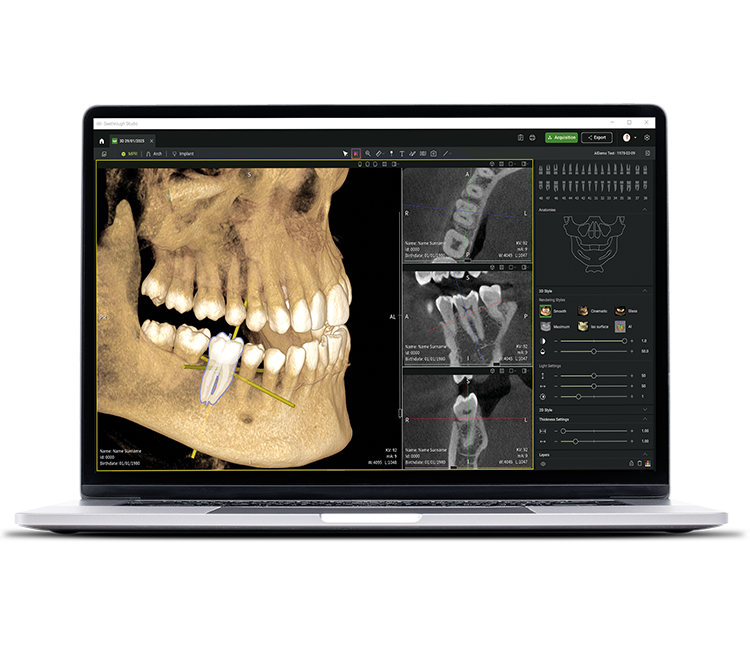

• Seethrough Studio

See tomorrow. See a new level.

Förutom sofistikerad hårdvaruteknik är den revolutionerande programvaran Seethrough Studio en avgörande faktor för den höga standarden på hela W&H-portföljen. Med sina fördelaktiga funktioner och avancerade algoritmer är Seethrough Studio en allt-i-ett-lösning som tar bildkvalitet och digitala tandvårdsarbetsflöden till en ny nivå.

Integrerat verktyg för implantatplanering

In addition to the outstanding image quality and intuitive operation, Seethrough Studio offers numerous useful features such as the standard integrated implant planning tool for easy visualisation and preparation of the treatment.

AI-stödda funktioner

Seethrough Studio utilises various AI tools for imaging enhancement, including 3D volume alignment, tooth segmentation, arch line generation, automatic nerve tracing as well as useful support for pathology detection.